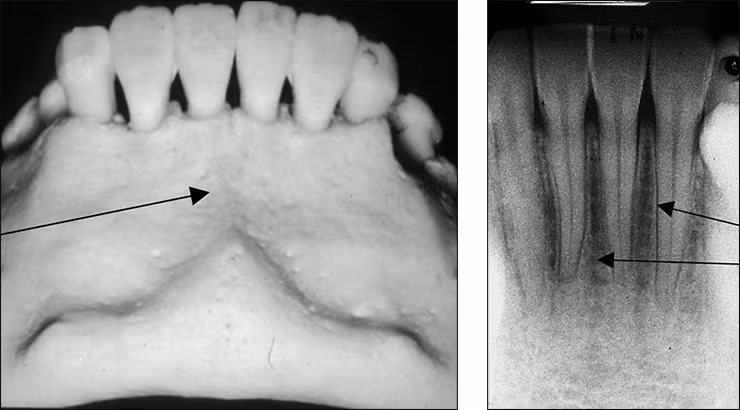

Lingual foramen – The lingual foramen is a small pin-point opening in bone on the lingual aspect of the anterior mandible for the lingual nerve and arteries (Figures 23 A&B). The lingual foramen appears in the midline below the apices of the central incisor teeth. This dot-like radiolucency is frequently surrounded by the genial tubercle. The lingual foramen is recorded on mandibular incisor periapical images.

Figures 23 A&B: Lingual Foramen